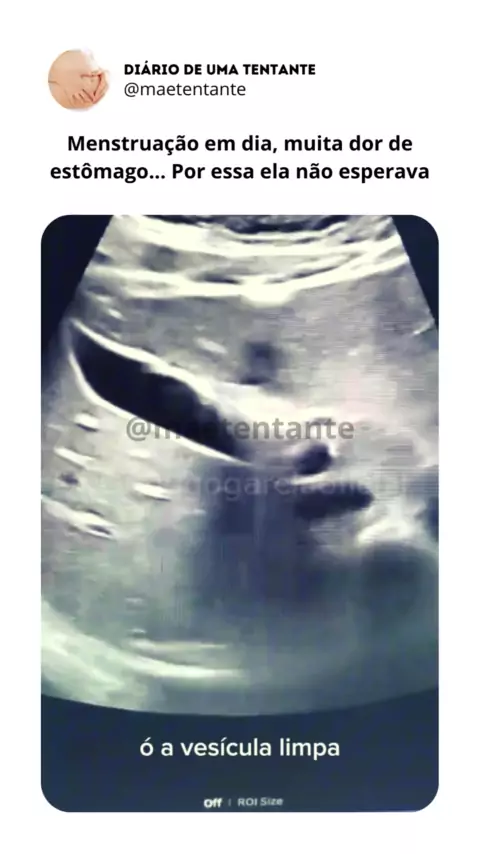

Por essa ela não esperava! #maetentante #gravidez #gravideznaoplanejada #gestante